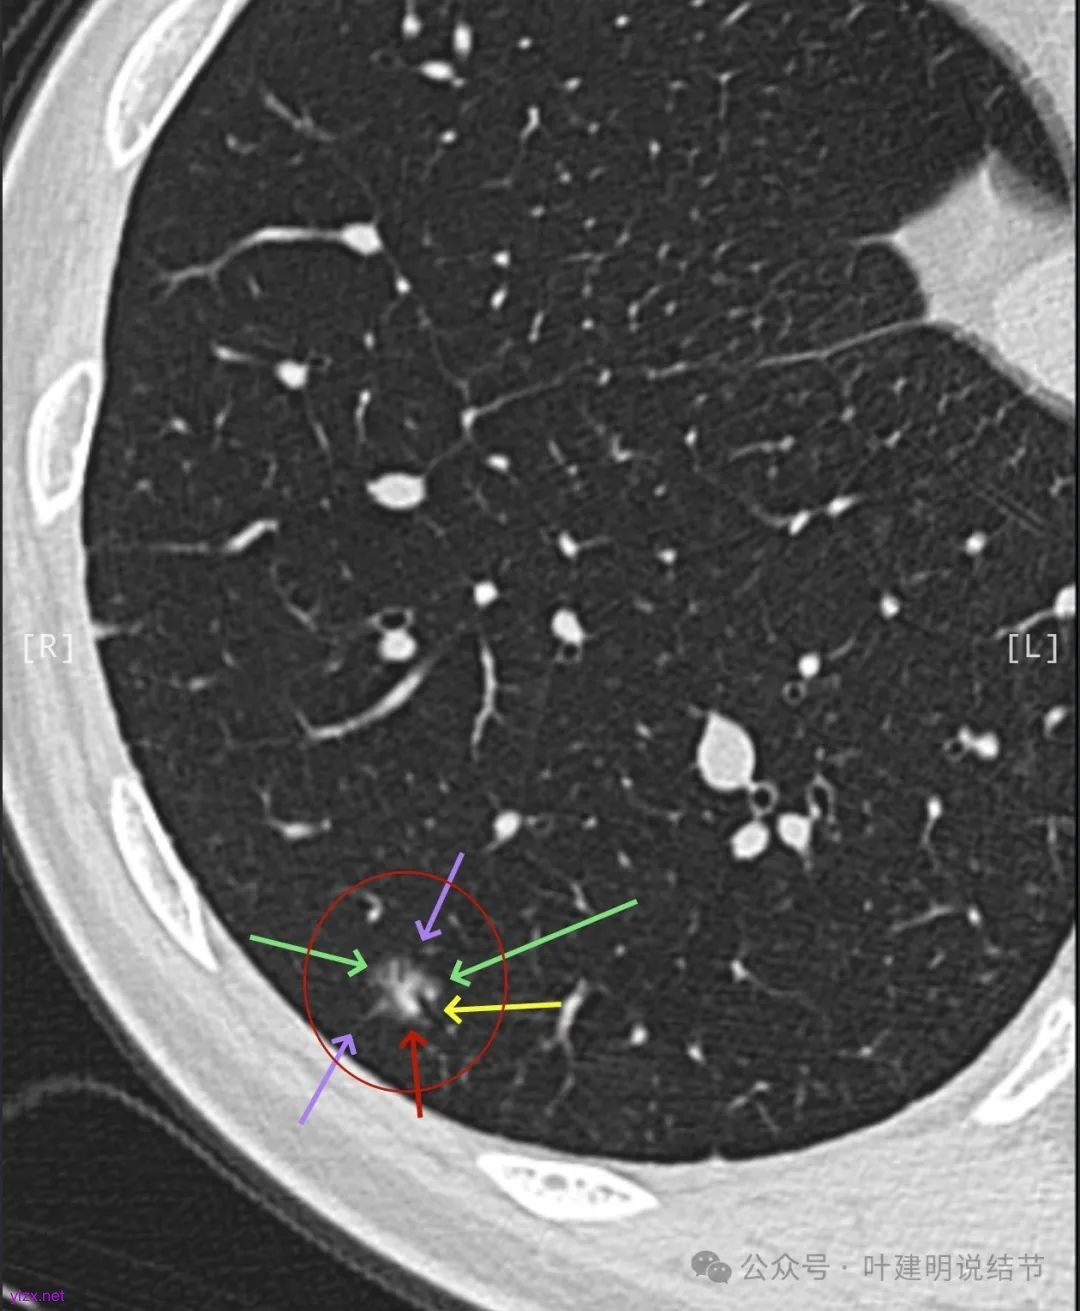

2024年9月时病灶较前有所增大,实性成分增大,表面不平,棘突明显,进入血管有异常增粗。

右下叶混合密度结节,随访略有进展,表面不平、边缘毛刺,有血管进入,整体轮廓与边界清,考虑是肿瘤范畴的,从进展缓慢来讲,恶性程度不高,应该是微浸润性腺癌或浸润性腺癌含贴壁与乳头型可能性大。由于位置好,能楔切,倾向考虑单孔胸腔镜下局部切了。意见供参考!

看了2017年的影像后,我又觉得病灶与附近炎性的形态类似,而且7年来进展也不厉害,慢性炎伴纤维增生的可能性也是有的。所以先半年复查,再有进展更像恶性再手术也可以。

逐层看了2024年的影像:

这个病例其实有反思回顾的价值,我想可以从中得出下面这些感想:1、混合磨玻璃结节随访持续存在且没有钙化或吸收好转,即使整体轮廓清,有血管征、有细支气管截断征、有毛刺与棘突征,且灶内密度杂乱,集齐许多恶性影像特征,仍不能下定论必为恶性;2、回头看病灶最终之所以不是恶性,而是慢性炎伴纤维增生与碳末沉积,最为关键的一是进展太慢,不符合混合密度结节含高密度实性成分的肺癌的生物学行为;二是实性部分密度过高而磨玻璃成分显得略偏模糊,看上去像有点晕征的味道。我反复总结过“混合密度实性成分过高而磨玻璃成分密度过低的容易是慢性炎或肉芽肿性炎伴纤维增生”。但临床的应用中仍不太敢下定论;3、多看几位医生也不能就100%明确。就如此例10位医生均考虑恶性范畴,虽有一位考虑原位癌,但其实也算是癌的范畴,但其实真正的影像上之所以判断的病灶部分不是肺癌,若牵强认为非典型增生与原位癌类似也可算浸润性病变,那也是碰巧而已,而不是从影像判断上看出有不典型增生,而密度高的却认定是良性成分;4、手术切除与否对于此例来说,仍是值得的,因为问了10位医生都说是肺癌,即使随访也压力巨大,而且密度不纯。从结果来看,已经存在非典型增生,继续随访,多年后也可能还是会发展成微浸润性腺癌或浸润性癌的可能性。而且楔切创伤不大,既明确诊断,也去除了病灶,是利大于弊的。当然这再次印证我一直坚持的原则:从风险高低来考虑手术与否以及干预的时机,而不要过于在意最后的病理结果。